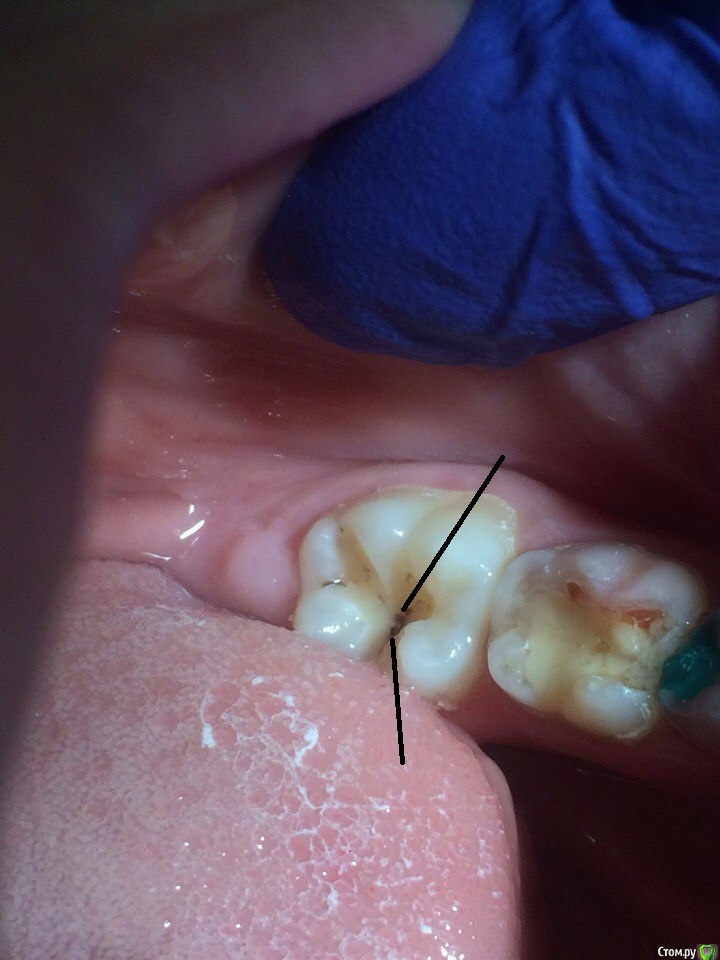

Wrestrus66 Опубликовано 12 октября, 2016 Поделиться Опубликовано 12 октября, 2016 Всем привет..Лечил 36 зуб , Кариес..стрелкой указанно место где очень болезненно , именно в этой точке ..Вопрос какую анестезию вы делаете в таком случае чтоб обезболить ?или же можно его так оставить зондом прошелся как по стеклу , но уже потихоньку зуб начал реагировать на холод но боль быстро проходящая..В итоге я так и оставил мед обработка хг2% , бонд , витример !Говорят витример хорош даже при кариесе , что под ним процесс дальше не пойдет т.к он выделяет Фтор ( не знаю на сколько это правда ) Большая проблема в анестезии Ссылка на комментарий

Джима Опубликовано 15 октября, 2016 Поделиться Опубликовано 15 октября, 2016 , если пИлите фиссуры, пилИте хотя бы бором "игла" тоненьким, красненьким. глазам больно... Ссылка на комментарий